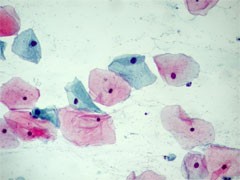

Die zytologische Untersuchung wird bevorzugt zur Früherkennung des Zervixkarzinoms eingesetzt.

- Exfoliatives Zellmaterial vom inneren und äußeren Muttermund des Gebärmutterhalses wird mit Hilfe einer Bürste vom Gynäkologen entnommen und auf einen Objektträger ausgestrichen. Wichtig hierbei ist eine schnelle Fixierung der Zellen mittels Fixationsspray. Im Zytologischen Labor werden die Zellen mit der Papanicolaou-Färbung angefärbt und nach der Münchener Nomenklatur III befundet.

Unaufälliges Zellbild Gruppe I